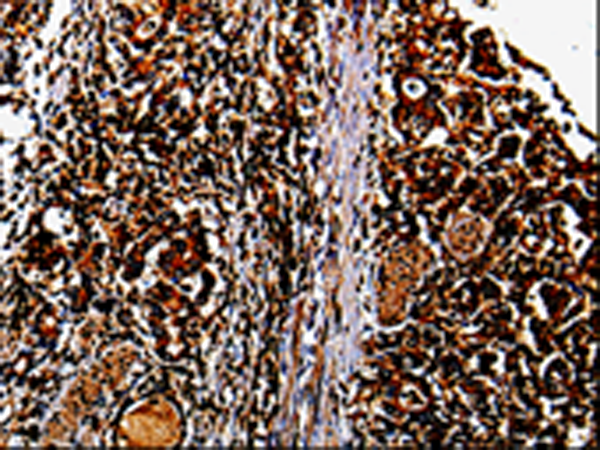

分类: 科研抗体货号: P00094别名: MGC104475应用: IHC反应种属: Human, Mouse